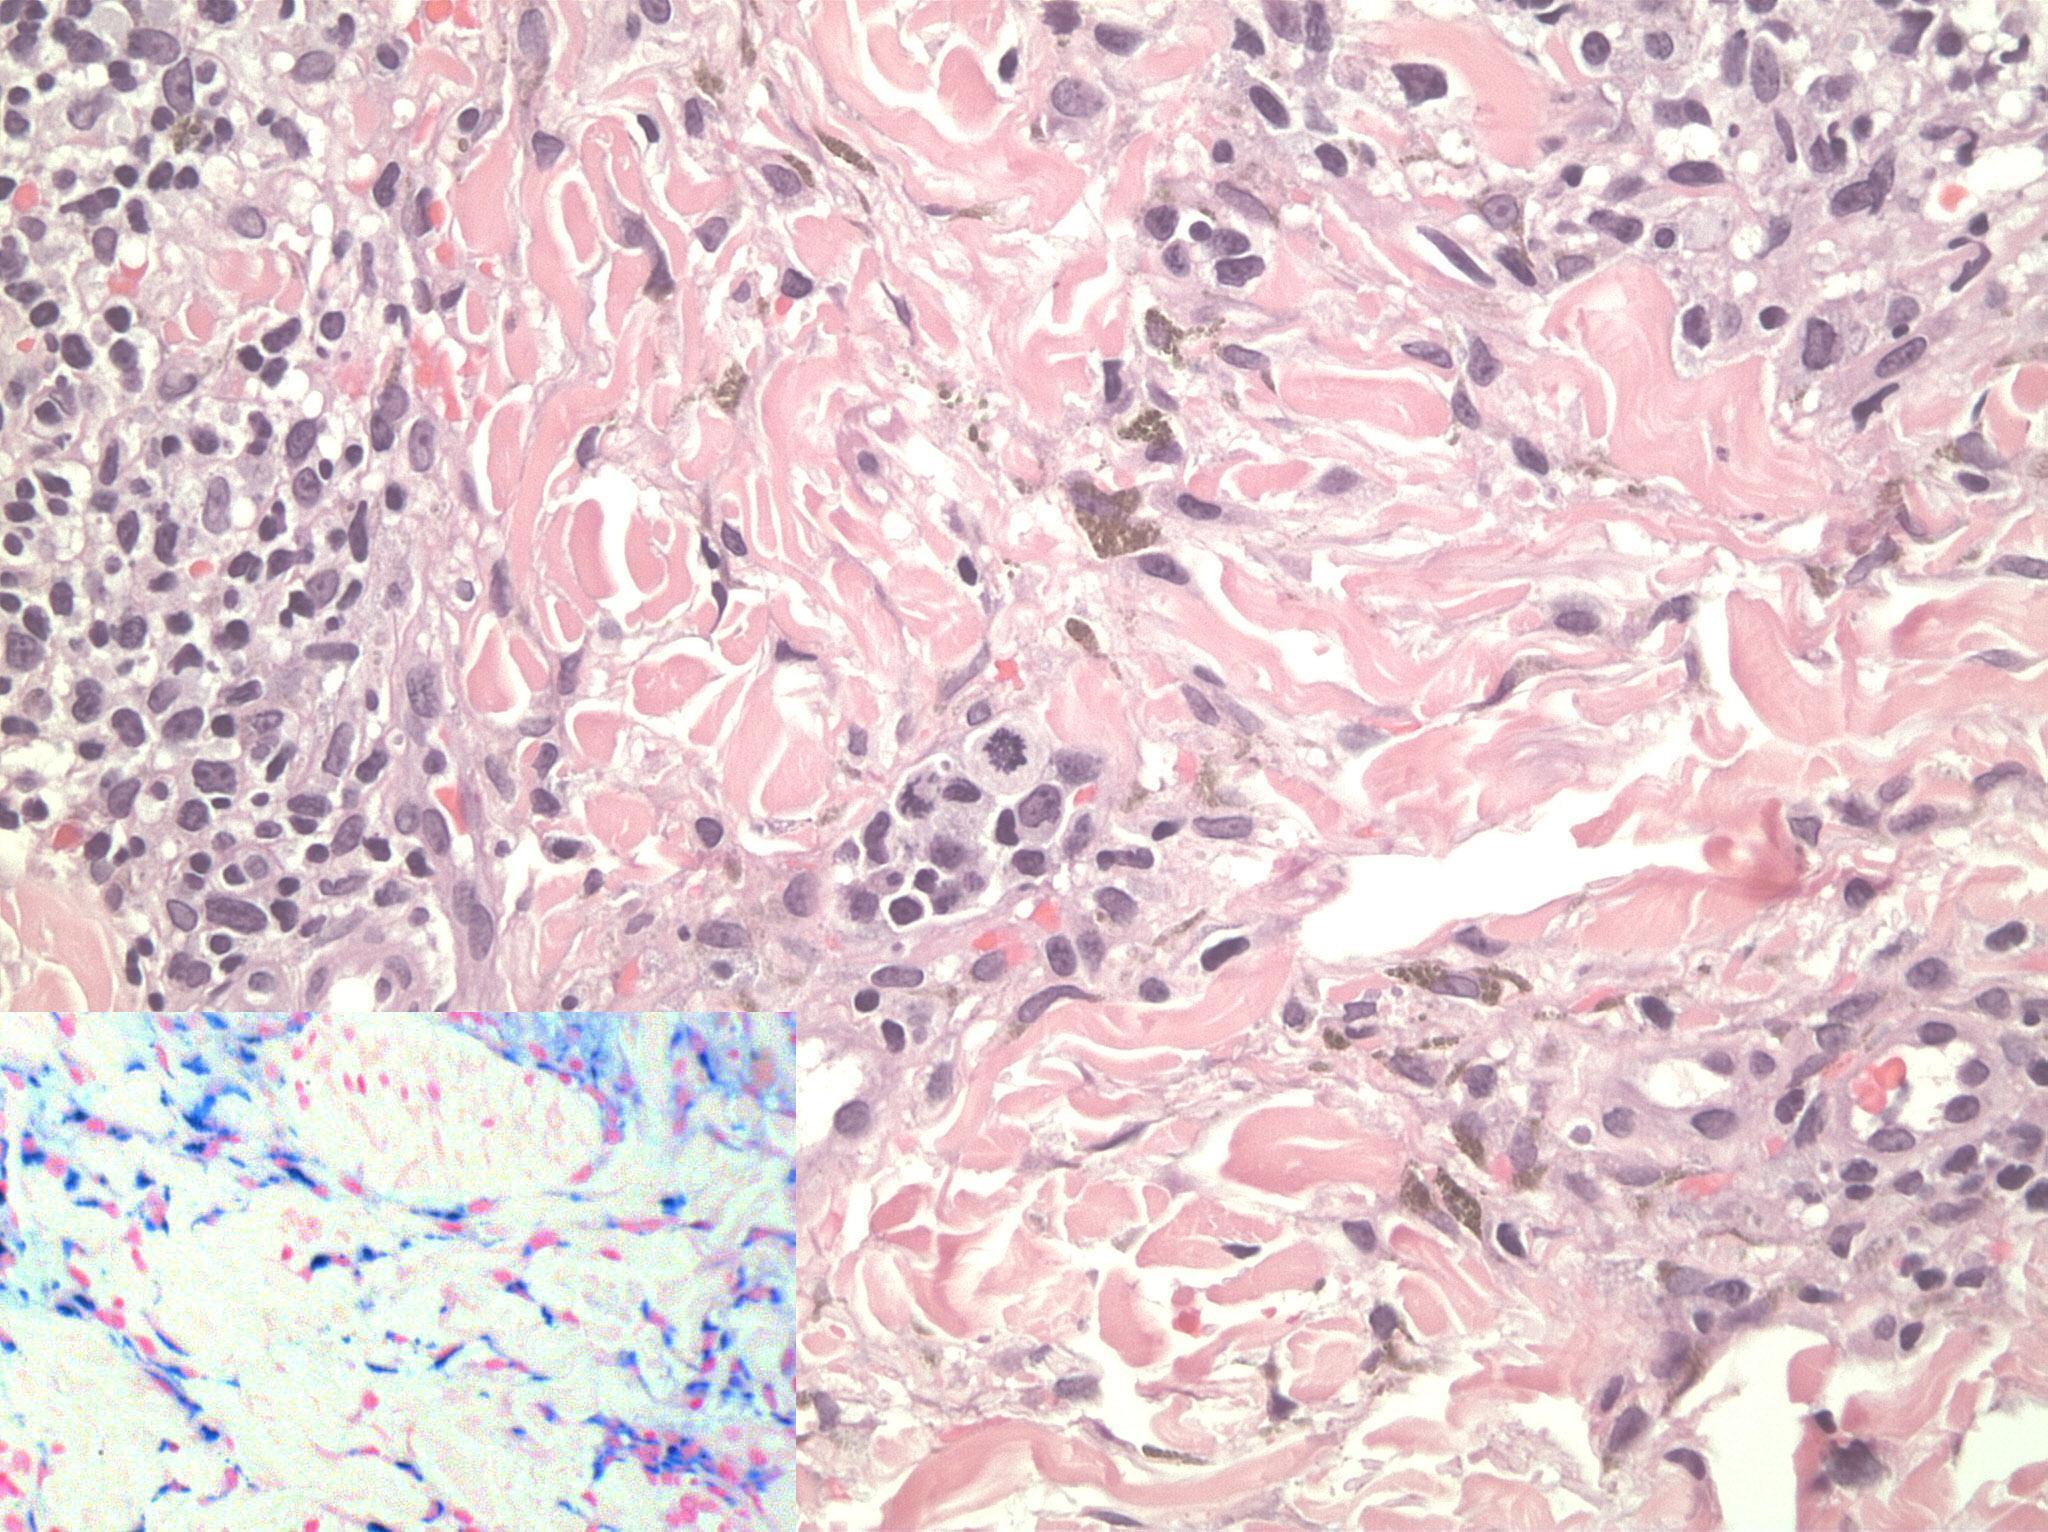

A 30-year-old man presented with a 4-month history of increased facial pigmentation. The patient reported that this had occurred 3 months after being started on oral isotretinoin (40 mg daily) for the treatment of acne vulgaris. He was otherwise healthy and not on any other drug therapy. In addition, he denied using any facial creams at the time when the problem had started. Moreover, he denied family history of similar condition or photodermatosis. On examination, the patient had well-demarcated hyperpigmented patches and plaques on an erythematous purpuric background (Figure 1). The changes were mainly observed on sun exposed surfaces. A punch biopsy was done and revealed dermal lymphohistiocytic infiltrates with scattered eosinophils, extravasated erythrocytes, and prominent hemosiderin deposition highlighted by iron stain (Figure 2). Fontana-Masson stain revealed no increase in melanin in the dermis or epidermis and immunohistochemical staining using MART-1 revealed normal melanocyte number at the basal cell layer of the epidermis.

Figure 2.Histology revealed dermal lymphocytic infiltrates with scattered eosinophils, extravasated erythrocytes, and hemosiderin deposition (original magnification, 20). Inset: Perl’s stain highlights hemosidrin depostion (original magnification, 40).